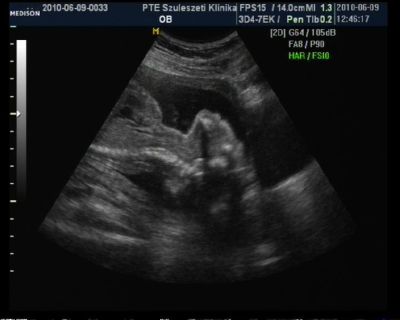

Az első két képen a drága szerszáma látszik!

Úgy feküdt a drága mint aki hátra bukfencet csinál doki is csak nézett.. de így a kukki lelógott :)

Mares de édes! Éna kukit nem látom....nem tudom mit kell nézni :oops: De a 3D-s kép nagyon ott van!

Mares! Jók a fotók :) bár a kukit én sem találom. Sőt a 2. 2d-s képnél meg mertem volna esküdni, hogy fej van, nyak és gerinc :)